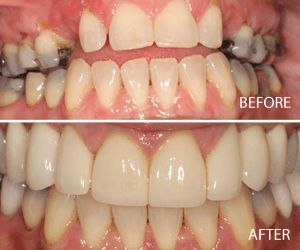

Comprehensive Cosmetic Makeover – Full Mouth